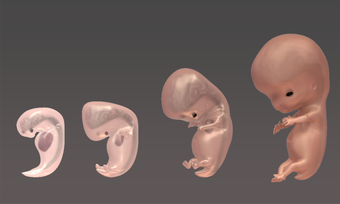

Esta aplicación está diseñada para ayudar a las madres y padres a entender los cambios que están ocurriendo en su cuerpo durante el embarazo. También está diseñada para ayudarles a hacer un seguimiento del desarrollo de su bebé en el útero. Es muy fácil de usar y la interfaz es muy simple e intuitiva. Muestra las etapas clave del embarazo desde la concepción hasta el nacimiento.

La aplicación está dividida en varias secciones, y cada sección contiene una descripción detallada y varios modelos 3D de alta calidad de las etapas clave del desarrollo del embarazo. Es muy fácil navegar por las secciones, y se puede cambiar entre ellas para ver diferentes etapas.